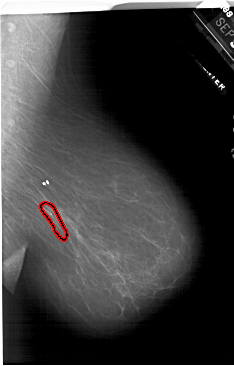

A_1850_1.RIGHT_MLO

RIGHT_MLO LINES 6571 PIXELS_PER_LINE 4201 BITS_PER_PIXEL 12 RESOLUTION 43.5 OVERLAY

FILE: A_1850_1.RIGHT_MLO.OVERLAY

TOTAL_ABNORMALITIES 1

ABNORMALITY 1

LESION_TYPE CALCIFICATION TYPE PLEOMORPHIC-FINE_LINEAR_BRANCHING DISTRIBUTION LINEAR

ASSESSMENT 5

SUBTLETY 3

PATHOLOGY MALIGNANT

TOTAL_OUTLINES 1

BOUNDARY